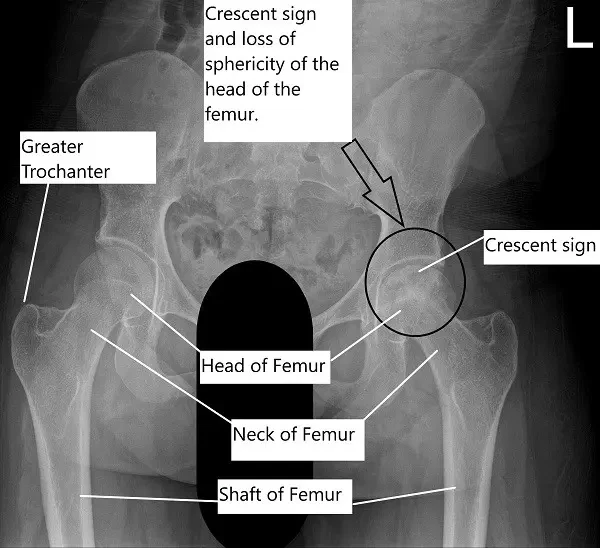

On radiological investigations, the X-ray of the left hip revealed avascular necrosis of the head of the femur with subchondral collapse visible in the form of a crescent sign. The X-ray of the right hip revealed a normal radiograph.

A CT without contrast revealed progression of the avascular necrosis since the core decompression surgery. Avascular necrosis involved the majority of the femoral head, most pronounced superomedially and measuring 3.1 x 3.8 cm.

There was a subchondral fracture superomedially and a mild collapse of the articular surface. There was a mild narrowing of femoral acetabular joint space superomedially with a suggestion of a small joint effusion.

The MRI of the left hip joint revealed a status-post core-decompression for left femoral head AVN. There was marrow edema surrounding the necrotic bone and suggestion of a subchondral “crescent sign” along with the superomedial femoral head, indicating fracture and stage III AVN. There was a slight focal collapse of the femoral head in this location.